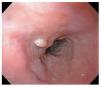

Se presenta el caso de un hombre de 45 años de edad que acudió a consulta por presentar pirosis y regurgitaciones de cinco años de evolución con respuesta parcial al consumo de inhibidores de la bomba de protones (20 mg a 40 mg de omeprazol en terapia a demanda). Por la cronicidad de los síntomas se le realizó una endoscopía del tracto digestivo superior en donde se encontró en el tercio medio del esófago una lesión exofítica de aspecto vegetante, con bordes bien delimitados y de color rosa blanquecino que midió aproximadamente 1 cm de longitud (Figura 1). Ante la sospecha de lesión papilomatosa asociada a virus del papiloma humano (VPH) se realizó biopsia excisional y se envió a estudio anatomopatológico. El resto del estudio endoscópico mostró esofagitis erosiva grado A de Los Angeles. Se prescribió tratamiento con omeprazol 20 mg dos veces al día por seis semanas. Por histología, la lesión presentó epitelio plano estratificado maduro con acantosis y papilomatosis (Figura 2), con centros fibrovasculares (Figura 3) dando un aspecto digitiforme. Las células basales eran grandes pero sin atipias nucleares, en los estratos superficial y medio las células mostraron maduración (Figura 4). Se realizó tinción de inmunohistoquímica para búsqueda de VPH la cual fue negativa (Figura 5). En el seguimiento se realizó endoscopía a los seis meses sin evidencia de recidiva de la lesión.

¿ Figura 1. Lesión exofítica de aspecto vegetante, con bordes bien delimitados de aproximadamente 1 cm de longitud.